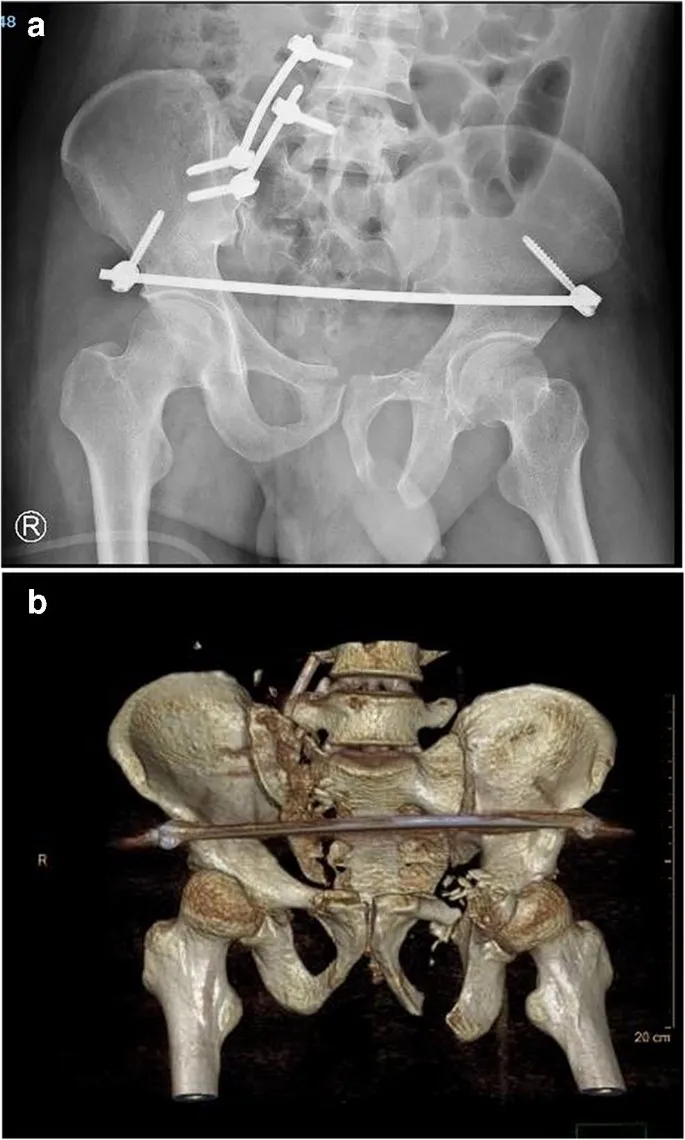

- Surgical Fixation (ORIF):

- Indicated for unstable fractures after the patient is hemodynamically stable.

- Goal: Restore pelvic ring integrity, enabling early mobilization.